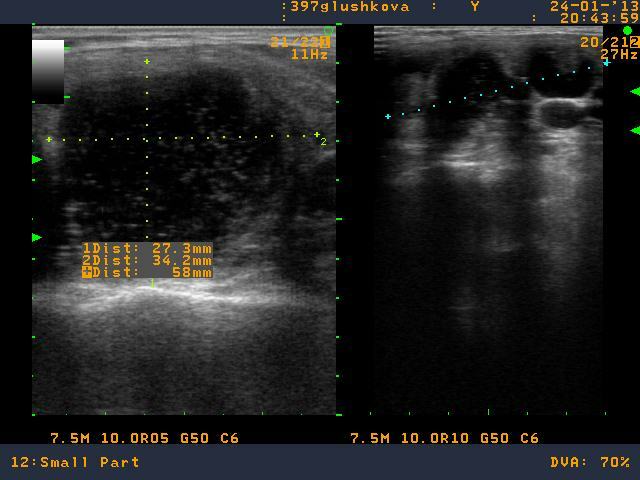

Несколько лет назад у пациентки была выполнена операция по поводу узлового зоба в объеме удаления правой доли щитовидной железы. На контрольном осмотре в поликлинике у пациентки выявлен узел в оставшейся доле щитовидной железы размерами до 30 мм. Эндокринологом поликлиники рекомендована биопсия узла правой доли щитовидной железы.

В Северо-Западном региональном эндокринологическом центре выполнена тонкоигольная аспирационная биопсия узла левой доли щитовидной железы. По результату биопсии щитовидной железы выявлена "Папиллярная карцинома щитовидной железы". Пациентке предложена операция, удаление левой доли щитовидной железы.